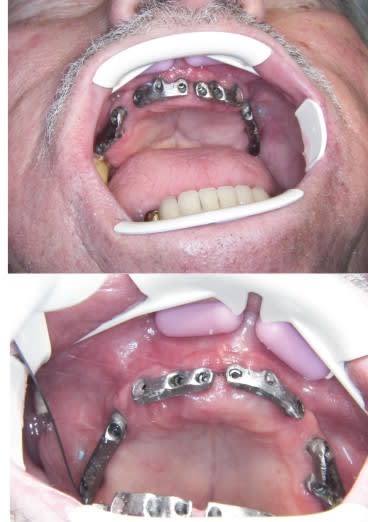

bonjour, je ne vois pas bien sur les cliches le type de prothese realisee. tu veux bien nous donner quelques details s'il te plait? merci

Dommage que l'environnement gingival en buccal des implants 13,12,11,21 et 22 semble défavorable en raison d'absence de gencive attachée.

Si tu ne pouvais pas placer l'émergende implantaire dans une position plus palatine, pourquoi ne pas avoir géré cela soit par chirugie muco ou bien par décalage palatin de l'incision d'abord crestal ?

prothese mile sur glissierres "maison" elle se clipse, le patient peut l'enlever et ça me permet de verifier la pérénité du changement DV et inversé d'occlusion.

si TVB, je pourrais passer au bridge ceramo metal si le patient le désire

l'ecarteur est un OptiView Kerr, stérilisable, et bien pratique.

tu as tout à fait raison.

j' ai eu du mal à gerer la partie implants (expansion de crête, et il etait important pour le patient d'avoir une prothèse.

je pense gerer la gencive maintenant, à l'abri de la prothèse.

dans ce cas j'avais prévu du 3,5 mm et lorsque j'ai placé 13 les implants en 12/11/21/22 sont devenus mobiles,(expansion de toute la crête) donc j'ai mis du 4 et fatalement j'ai perdu la distance inter implant qui etait déja réduite.